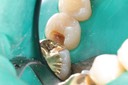

Scott Kanamori #31 pre-op

Scott Kanamori #31 amalgam removal